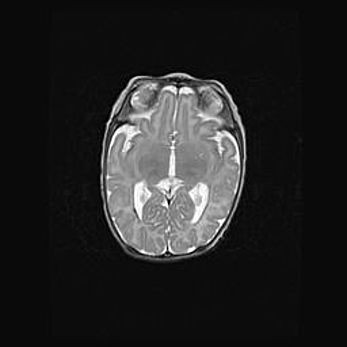

Лейкомаляция с кистозно-глиозной дегенерацией головного мозга.

Возраст: 2 месяца 25 дней

Вес: 6400 г

Окружность головы: 40 см

Срок гестации: 41 неделя

Лейкомаляцию относят к ишемически-гипоксическим повреждениям головного мозга, диагностируемым у новорожденных. При лейкомаляции в головном мозге обнаруживают очаги некроза, возникшие после тяжелой гипоксии и нарушения кровотока. В процессе морфогенеза очаги проходят три стадии: 1) развития некроза, 2) резорбции и 3) формирования глиозного рубца или кисты. Перивентрикулярная лейкомаляция (ПЛ) встречается примерно в 12% случаев среди новорожденных, обычно – у недоношенных детей, причем, частота ее зависит от массы, с которой младенец появился на свет. Наибольшее число малышей страдает лейкомаляцией, если масса при рождении 1500-2500 г.